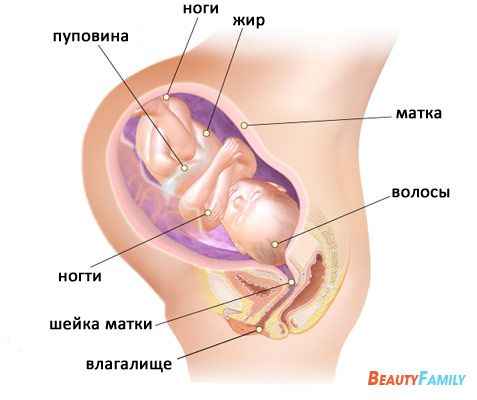

На 38 тижні вагітності середня вага дитини в утробі становить 2,9 кг. Ваш конкретний дитина може важити від 2,7 до 3,6 кг в даний час.

У цей період кожна дитина особливий і має свій унікальний вагу і зріст. На цьому тижні довжина вашої дитини може становити від 48 до 51 см з голови до п'ят. У найближчі тижні довжина дитини практично не зміниться.

Рівень амніотичної рідини в матці неухильно знижується на 38 тижні вагітності. Постарайтеся не турбуватися, ваш малюк все ще має достатню кількість навколоплідних вод, щоб він був у безпеці. Місця для переміщень в утробі стає все менше, але дитина як і раніше буде штовхати вас і намагатися пересуватися.

На той час як ви досягнете 38 тижні вагітності, кістки рук і ніг малюка вже зміцніють. Кістки черепа будуть м'якими до самих пологів, і почнуть зміцнюватися вже після народження дитини.

У 38 тижнів вагітності у дитини є цілком сильний рефлекс схоплювання. Він або вона проводить свій час, схоплюючи і стискаючи пуповину.

Легкі Вашої дитини повністю сформовані. Починаючи з 37 тижня вагітності і до самих пологів малюк вже сформований і в утробі тільки набирає вагу. Це може тривати ще кілька тижнів. Будьте терплячі, ваша дитина народиться в найближчим часом.